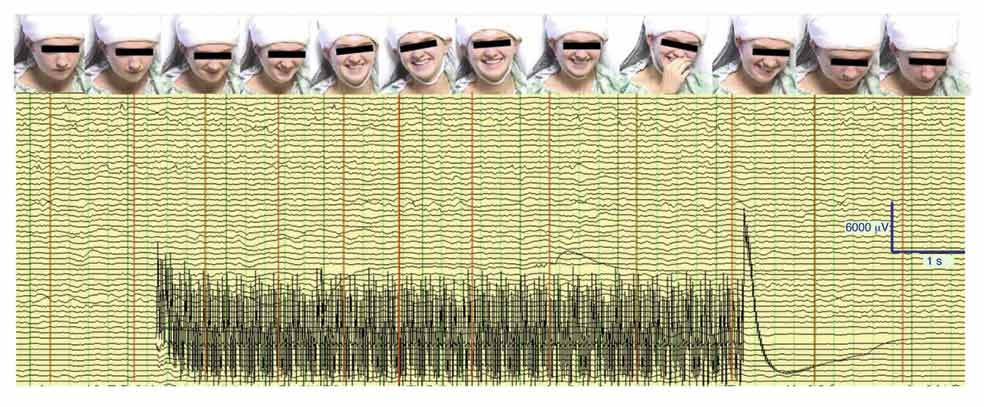

Lleva una especie de casco blanco y está semiincorporada en una cama de hospital. De pronto se ríe con entusiasmo. «No puedo evitar reír», dice entre carcajadas. «¿Qué sientes?», le preguntan. «Una sensación buenísima. Increíble», contesta. Es una chica de 23 años que padece epilepsia desde los 14 y que ha accedido a participar en unas pruebas organizadas por neurocientíficos de la Escuela de Medicina de la Universidad de Emory, en Atlanta (Estados Unidos).

«Piensa en algo triste», le piden. La chica sigue sonriente. «¿Has pensado algo triste?», le insisten. «He recordado la muerte de mi perro. Me he concentrado en malos recuerdos, pero no los puedo sentir como tristes, aunque sé que lo son», cuenta con una amplia sonrisa.

La investigación, en la que participaron otros pacientes con epilepsia, demostró que, cuando se estimulaba eléctricamente el haz del cíngulo–manojo de fibras que discurre en la materia blanca del giro cingular del cerebro–, los pacientes sentían alegría y bienestar, incluso al recordar momentos tristes.

Los investigadores no buscaban el punto cerebral que dispara la felicidad, sino que estudiaban la epilepsia; buscaban la fuente neuronal de sus convulsiones. Lo que hallaron de manera casual es que la estimulación eléctrica del haz del cíngulo hacía reír y sentirse felices a quienes recibían esos estímulos. La chica de 23 años incluso contó chistes de carrerilla tronchada de risa.

Los tres pacientes que se sometieron a esta prueba, además, percibían todo con espíritu jubiloso. Les mostraron distintas caras, felices, tristes y neutrales, para que las calificaran y a ellos –siempre sonrientes y relajados– les parecían todas ufanas. Veían la vida con mejores ojos.

Los investigadores de Emory decidieron comprobar entonces hasta qué punto esos pacientes repentinamente alegres con electrodos conectados en el haz del cíngulo conservaban su nivel de cognición. Les hicieron pruebas de memoria, atención y lenguaje y comprobaron que la estimulación que les hacía sentir tan bien no interfería en su capacidad de análisis.

Ya lo han probado. El conejillo de Indias fue de nuevo la chica de 23 años. Le practicaron una cirugía relacionada con su epilepsia mientras ella estaba consciente. Los resultados fueron positivos: la chica estuvo sonriente y permaneció relajada y tranquila durante la intervención.

Dar sosiego a los que deben ser operados despiertos es una importante ayuda. «Incluso los pacientes bien preparados pueden entrar en pánico durante la cirugía en vigilia», dice Kelly Bijanki, profesora de Neurocirugía de Emory y participante en la investigación. Una utilidad –tranquilizar en cirugías sin sedación– ya está probada. Las demás no son tan sencillas de certificar. No es tan fácil como decir «este es el botón del cerebro que nos hace feliz», lo pulsamos y todos contentos. Tendemos a simplificar demasiado, alertan los científicos.